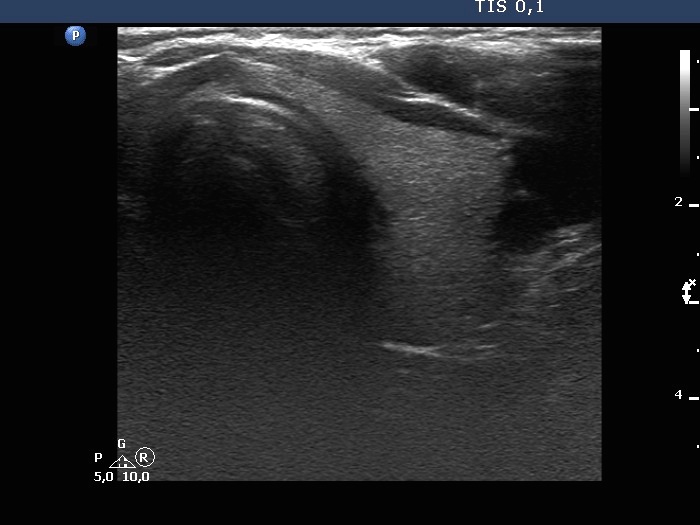

The composition of the nodule - case 1579 (ultrasonographic picture 4)

Right lobe, longitudinal scan